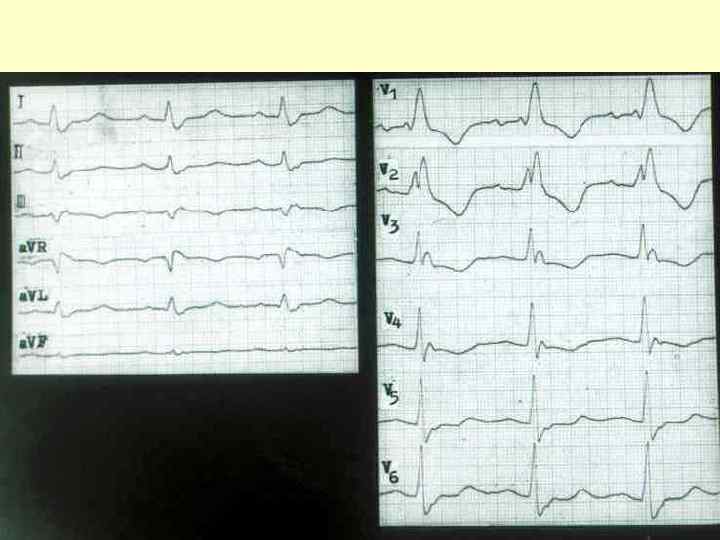

Блокада левой ножки пучка Гиса

Блокада левой ножки пучка Гиса.